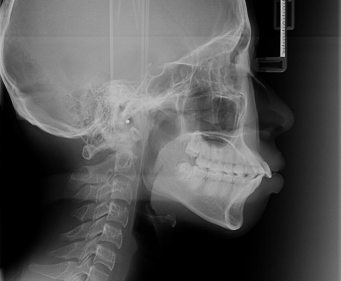

整牙为什么需要拔牙?

1、牙列严重拥挤

2、侧貌凸

3、咬合不良